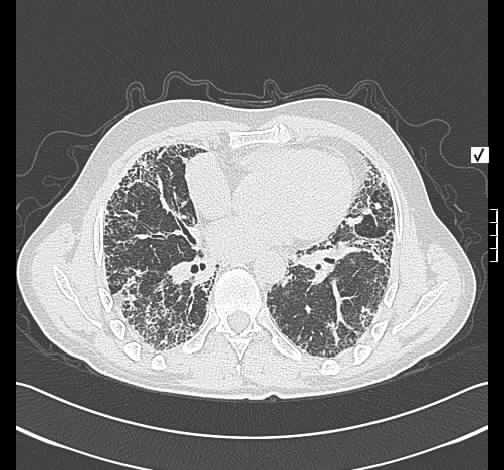

A 57-year-old patient was referred to our clinic because of unproductive cough and progressive dyspnea. High-resolution computertomography (Panel A) showed irregular reticular pattern (a), honey combing (b), pleural thicking (c), bronchiectasis (d) and was therefore highly suggestive of usual interstitial pneumonitis (UIP) (1,2). Because medical therapy (corticosteroids, acetlycysteine and azathioprin) could not stop disease progression, the patient was referred for bilateral lung transplantation (B-LTX).

Radiologisch stellt sich eine interstitielle Lungenerkrankung dar. Man sieht eine peripher und unterlappen-betonte retikuläre Zeichnungsvermehrung mit Unterlappenschrumpfung. Im HRCT ungleich verteilte, peripher betonte retikuläre Zeichnugnsvermehrung mit Honigwaben-Muster, beginnende Traktionsbronchiektasen, Pleuraverdickung, keine Milchglas-Infiltrate. Zusammenfassen lassen sich die radiologischen Befunde sehr gut mit einer idiopathischen pulmonalen Fibrose IPF/UIP vereinbaren.

Im HRCT ebenfalls eine diskontinuierlich verteilte, peripher- und unterlappen-betonte retikuläre Zeichnungsvermehrung mit Pleuraverdickung, Honig-Waben-Muster und beginnenden Traktionsbronchiektasen.

Der radiologische Befund ist sehr gut mit einer idiopathischen pulmonalen Fibrose IPF / UIP vereibar.